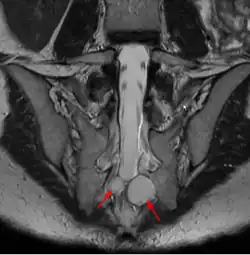

Un kyste de Tarlov (KT) ou kyste périneural, est une dilatation locale de l'espace sous-arachnoïdien se formant au contact d'une racine nerveuse, le plus souvent sacrée, dans la zone de transition entre arachnoïde et périnèvre (membrane externe du nerf). Il est fréquent et le plus souvent asymptomatique, mais peut parfois causer des symptômes neurologiques : on parle alors de maladie de Tarlov.

Quel que soit le système de classification, la définition d'un kyste de Tarlov est histopathologique car elle nécessite la présence de fibres de racines nerveuses de la colonne vertébrale dans la paroi du kyste ou dans sa cavité. Les kystes de Tarlov sont définis comme des lésions sacciformes, remplies de liquide cérébrospinal (LCS), situées dans l'espace extradural du canal spinal sacré et formées à l'intérieur de la gaine de la racine nerveuse au ganglion de la racine dorsale.